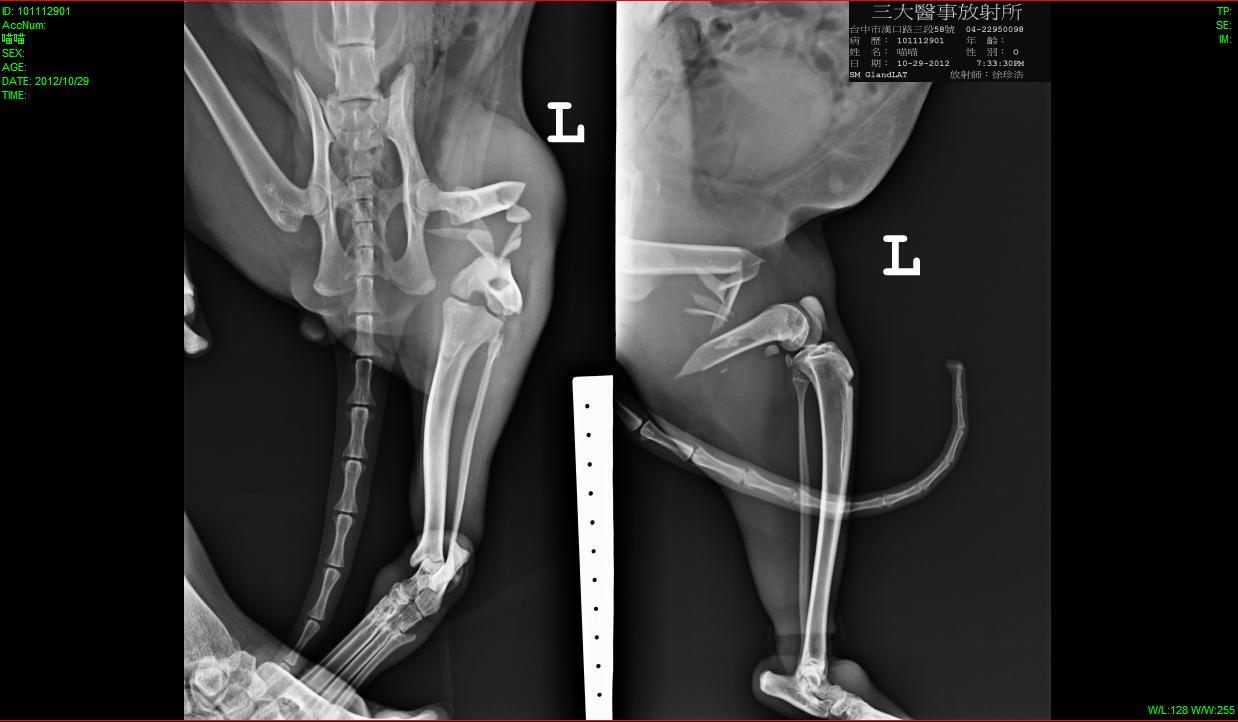

主題: 腿斷的喵喵需要大家幫忙出醫藥費 申請者姓名: 邱依如 花色: 申請日期: 2012-11-09 00:24:12 申請者部落格: 申請者臉書網址: 所在縣市/合作醫院: 台中市/崇德動物醫院 治療費用: 7500元 需求人數: 17人 已結案 (2013-06-27 14:03:59) 報名人員: 林廷軒(已付款)、Zheng Ivis、Elsa Tu(已付款)、Xarier Huang、Alex Chang(已付款)、Lancelot H. C. Lee(已付款)、Kaye(已付款)、Hui - Lan Zhuang(已付款)、Olive Chen(已付款)、Yuching Wang(已付款)、w691010(已付款)、shuwen(已付款)、Zheng Ivis(已付款)、嘟嘟(已付款)、嘟嘟(已付款)、嘟嘟(已付款)、嘟嘟(已付款)、Kuen-Lin Tsai(已付款)、臺北市支持流浪貓絕育計劃協會(代楊姍珊報名)(已付款)、 候補人員: 動物病情說明: 這隻白底虎斑貓是我餵養區(霧峰國小)已經TNR的貓咪~

10/28我去霧峰國小打球完順便餵貓的時候百姓公廟的大哥趕緊跟我說貓咪被三四隻野狗追趕,後來回來腿就好像斷掉不能走了!!

隔天星期一我就快點帶去崇德動物醫院檢查與治療~

現在手術很成功~每週回去檢查到可以拔釘~

只是往後牠會長短腳不好跑...